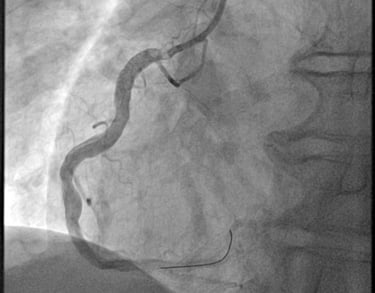

ANGIOPLASTICA

Angioplastica coronarica e lo stent

Si tratta del piu' comune trattamento attualmente utilizzato per curare l'aterosclerosi coronarica. E' una metodica che si avvale di molteplici strumenti appositamente ideati e realizzati e puo' essere effettuata subito dopo la coronarografia, utilizzando la stessa via di accesso arterioso. Solitamente, il paziente sottoposto ad angioplastica coronarica programmata puo' essere dimesso il giorno successivo alla procedura. Lo stent coronarico e' un dispositivo di grandezza millimetrica, in lega metallica biocompatibile (quindi senza fenomeni di rigetto), che viene utilizzato di solito dopo la dilatazione dell'arteria coronarica con il palloncino, per mantenere la pervietà della arteria.